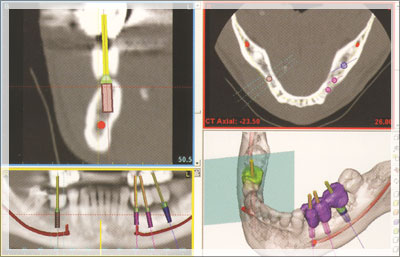

当院では、インプラント術前シミュレーションソフト

「3Dコンピューターシミュレーションシステム」を使用しております。

3Dコンピューターシミュレーションシステムは、CT撮影のデータを再構築し、3方向画像や3D画像により、

多面的に各種測定やインプラント埋入シミュレーションができるソフトです。

細かく治療計画を立案し、リスクを抑えて手術に挑むことができます。

患者さまの負担の軽減と審美性を第一に考え、3Dコンピューターシミュレーションシステムを活用してインプラント治療を行っております。

顎骨形態、骨質を3次元で解析します。数値と画像で精密な情報を把握。

実際の手術をアクティブに再現します。審美・機能の改善を入念にシミュレートしていきます。